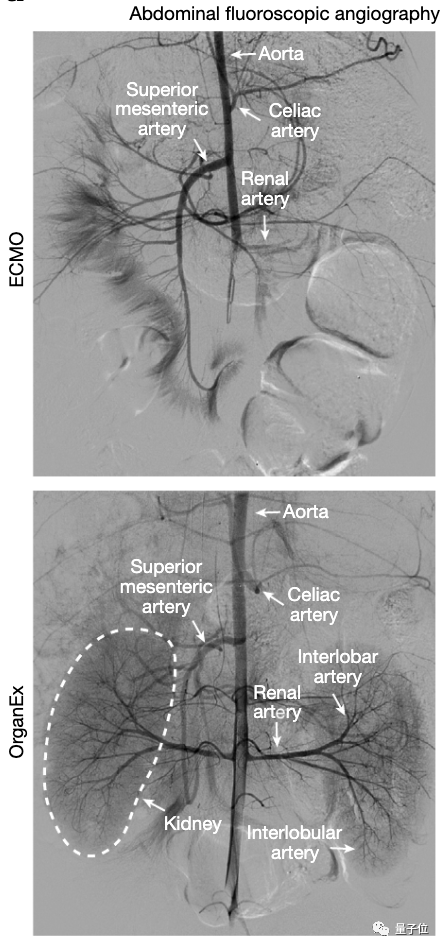

OrganEx比“人工肺”ECMO复杂一些,除了心肺,还模仿了肾的功能,具体包括离心泵、脉冲发生器、血液透析滤过仪、气体输注/药物输送系统和传感器(用于测量代谢和循环参数)

结果是OrganEx成功在小猪体内恢复了全身血液循环,各处动脉和器官(心脏、脑、肾和肝等)保持“充盈”状态,在ECMO则只能看到非常有限的此类现象。